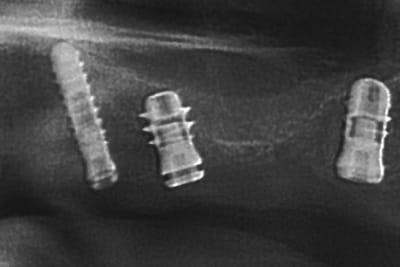

allez, dans ma série, "je remets des sujets" je vous donne quelques nouvelles de ce cas

la raison et vos conseils me sont revenus, j'ai posé hier 2 implants supplémentaires en 17 et 27 (sans les facturer à mon patient)

ce qui me frappe, tout de même, avec les quelques radios prises, c'est la cicatrisation osseuse au niveau de ceux en 15 et 25 (cf panos jour de la pose/3mois/4mois et les "zooms" pose/4mois)

la nature est parfois très sympa...;-)